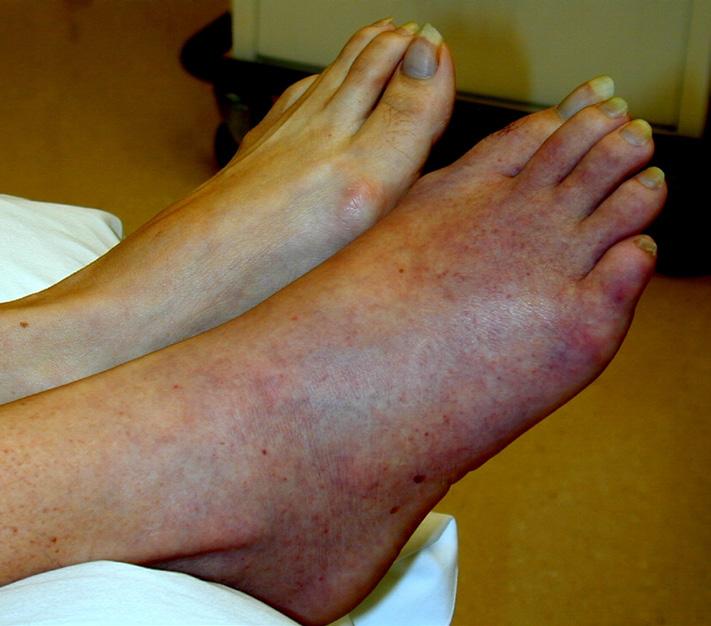

Endometrial cancer is the most common gynaecological malignancy in the first world, with incidence rising in parallel with obesity, metabolic disease, and population ageing.

General practitioners play a pivotal role in early recognition, investigation and referral as prognosis is strongly linked to stage at diagnosis. The majority of endometrial cancers are cured, usually by surgery alone.

Epidemiology and risk factors

Endometrial cancer primarily affects postmenopausal women, with a median age at diagnosis of approximately 60 years. However, up to 10% of cases occur in premenopausal women, including a small proportion under the age of 40.

The dominant risk factor is unopposed oestrogen exposure. This may be endogenous (e.g. obesity, polycystic ovary syndrome) or exogenous (e.g. oestrogen-only hormone replacement therapy). Additional risk factors include: